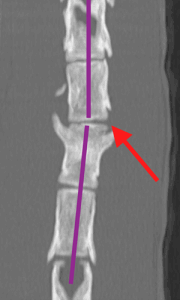

Osiris presented to Hamilton Specialist Referrals (HSR) as an emergency following a fall from height. Sadly, he was unable to use his back legs. His first opinion veterinary practice promptly identified that Osiris was paraplegic and acquired some radiographs of his back. These revealed a high suspicion of a spinal fracture at the location identified by the red arrows on the below images.

Osiris was assessed by our anaesthesia team and nurses who stabilised him so that he could be anaesthetised. Under a general anaesthetic, a CT of the back confirmed the fracture in his spine (red arrow on images below). The vertebral canal (green star) is where the spinal cord runs. The floor of the vertebral canal (blue lines) should be level and as you can see in the images there is a step in the floor, resulting in pressure on the spinal cord. The image on the right also shows a deviation in the spine (the purple lines should be straight), also adding pressure to the spinal cord. This pressure means that the neurotransmission pathway between the brain and legs is disrupted, which ultimately meant that Osiris couldn’t use his hindlimbs.